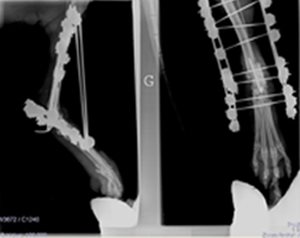

Ostéosynthèse Unilock du rachis chien

Fracture du corps de L5 avec déplacement lombaire ventrale. Ostéosynthèse par plaque Unilock avec implantation des vis dans la racine des apophyses épineuses.

L'examen neurologique préalable indiquait une sensibilité douloureuse conservée avec préservation des motoneurones périphériques.